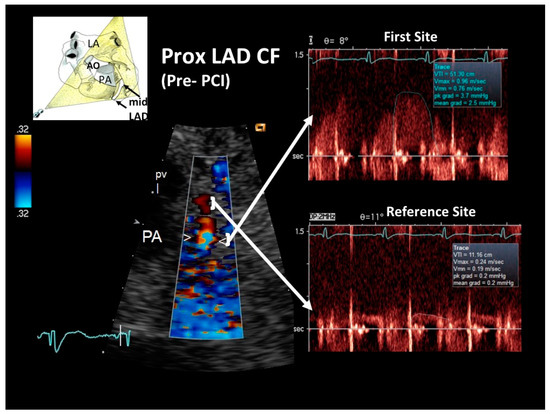

General echocardiography revealed marked apical and anterior septal wall hypokinesia, with a globally preserved left ventricular systolic function but marked telediastolic restriction, as assessed by pulmonary venous flow Doppler recording. The latter showed a high peak and markedly prolonged duration of reversal of pulmonary venous flow [17]. E-Doppler TTE allowed a flow velocity Doppler recording to be made in the LMCA and in the entire LAD. Findings were markedly abnormal, recording a locally accelerated and turbulent flow at the end of the proximal LAD tract, as revealed by color-guided PW Doppler recording indicating significant stenosis (Figure 2). By applying the continuity equation, which has been amply validated with this approach [12,13,18], the stenosis was quantified as severe (89% of area reduction). Coronary flow reserve (CFR) was not measured due to the critical setting.

Figure 2. Blood flow Doppler recording by E-Doppler TTE in the proximal LAD, offering a modified short-axis view of the base of the heart in the acute phase. On the left, color flow in the proximal LAD shows a limited area of considerably accelerated BFV expressed by aliased signals (arrowheads); some flushing artifacts are also present since the heart rate was suboptimally reduced, but they do not disturb the proper signal interpretation. PW Doppler sampling (on the right) at the color-aliased signal confirms a critical increase of blood flow velocity compared to the distal reference area (upper and lower arrows connect the sampling color area to the corresponding PW Doppler tracing). Application of the continuity equation yields an 89% stenosis area. A cartoon indicating the plane orientation is shown on the upper left. The diastolic waves of the Doppler tracings are outlined in blue. LAD = left anterior descending coronary artery; PW = pulsed wave; CF = coronary flow; RVOT = right ventricular outflow tract; PV = pulmonary valve; PA = pulmonary artery; LA = left atrium.